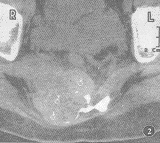

病人,女,20岁。右骶部疼痛性包块伴鞍区麻木3个月。3个月前无诱因感骶部隐痛,右侧骶部隆起,渐出现二便障碍。体检:鞍区浅、深感觉减退,四肢肌力Ⅴ级,右骶部触及肿块大小约5 cm×5 cm,质硬、固定,压之疼痛及鞍区麻木加重。B超检查:子宫右后方探及6.9 cm×4.0 cm大小低回声包块,边缘清楚,内部回声均匀。X线检查:骶3~5右侧骨质膨胀性破坏,边缘清楚,无明显硬化(图1)。CT检查:骶骨右侧明显骨质破坏,可见约6.5 cm×5.6 cm大小的巨大软组织块,分叶状,境界清楚,密度不均匀,CT值22~64 HU,有小点状钙化,肿瘤有网格样增强(图2)。MRI检查:骶3~5右侧膨胀性骨质破坏,可见约8 cm×6 cm×6 cm大小的囊实性肿块,边缘清楚,囊性占大部分,呈多房状,囊性部分呈长短T1混杂信号,T2信号不均匀明显增高,T2WI可见多个液平,其间隔呈长T1短T2信号。直肠向左前推移。子宫右侧可见一类圆形长T1长T2信号(图3)。DSA检查:骶骨前方可见增粗,紊乱之肿瘤血管网,动脉呈瘤样扩张。

图2 CT示骶骨右侧骨质破坏,可见约6.5 cm×5.6 cm大小分叶状软组织肿块